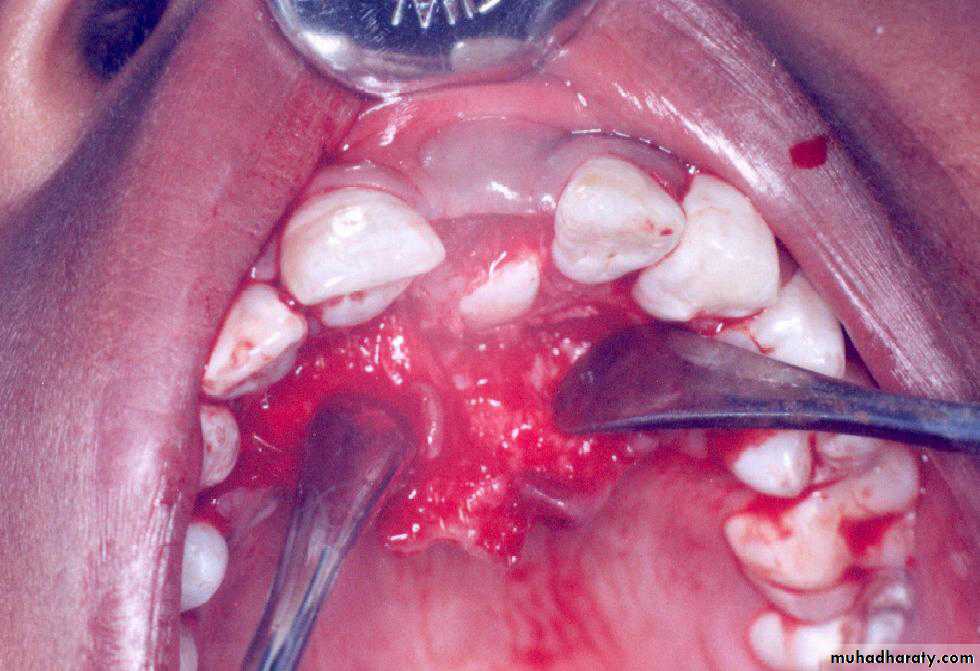

Surgical exposure :the path of eruption is not obstructed

Surgical exposure with orthodontic traction: the path of eruption is obstructed

Surgical exposure with orthodontic treatment (palatal approach )